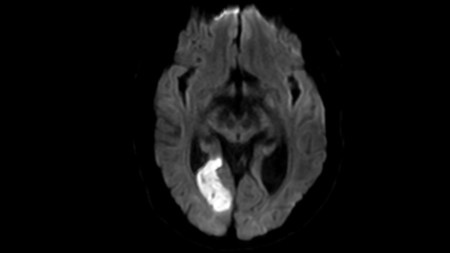

Improved nutrition and physical activity will directly decrease the burden cardiovascular disease and diabetes in a modern society, reducing the need for medical intervention and improving patient outcomes.